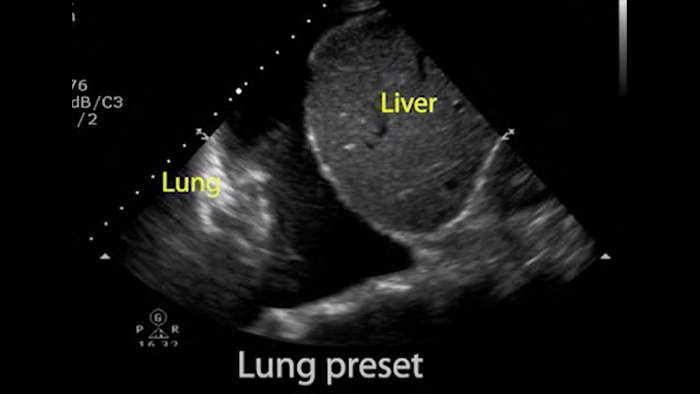

Lumify für die Beurteilung der Atemwege und Lungen

Die Lumify Point-of-Care-Ultraschalllösung kann die Erkennung des Endotrachealtubus in der Trachea erleichtern, Koniotomieverfahren unterstützen sowie bei der Diagnose von Pleuraerguss und interstitiellen Alveolarerkrankungen helfen.

Basics of lung ultrasound (Grundlagen des Lungenultraschalls)